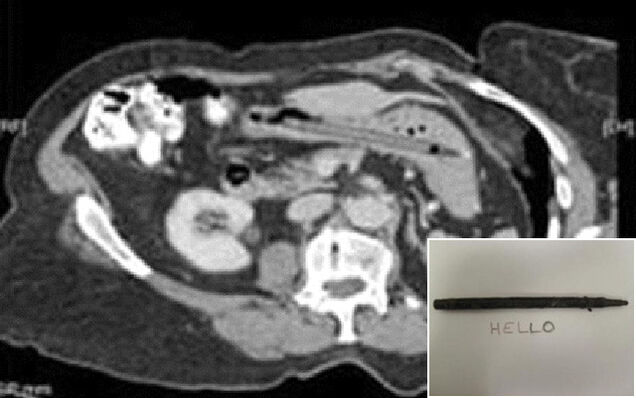

I have a cup on my desk filled with approximately two dozen pens, which at any given time yields a total of maybe one working writing instrument whenever I need it — usually a dull pencil or crayon. That's just my crappy luck. So you'll forgive me if I experience just a twinge of envy when relaying the tale of the 76-year-old woman from England who checked herself into a gastroenterologist's office complaining of diarrhea, only to learn from an CT scan that she had been carrying around a pen inside her for approximately 25 years. And it still wrote.

On subsequent questioning, she recalled unintentionally swallowing a pen 25 years earlier. While she was interrogating a spot on her tonsil with the pen she slipped, fell and swallowed the pen by mistake. Her husband and general practitioner dismissed her story and plain abdominal films done at the time were reported as normal.

The case was apparently then discussed at the hospital's gastrointestinal multi-disciplinary meeting and a decision was made that the pen — while it had no bearing on the runny stools that brought her into the hospital in the first place — should be removed for the woman's own safety. An endoscopy successfully got it out, and visual evidence of the writing instrument's enduring potency was captured. A triumph for the felt-tip pen manufacturing industry, to be sure! [casereports.bmj.com via NY Daily News, Images via BMJ]